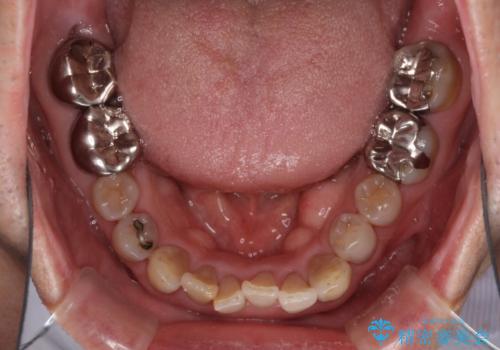

上顎の狭窄歯列 インビザラインによる拡大矯正

- 前歯の叢生と臼歯のクロスバイトを気にして来院された患者様です。

急速拡大装置による上顎の側方拡大を行い、その後はインビザラインより歯列を改善することとしました。

20代後半以降の男性は上顎骨の側方拡大処置の成功率が低く、今回も骨を拡大することができませんでした。

しかしながら、歯列を側方に拡大することができ、その後はインビザラインにて叢生を解消することができました。